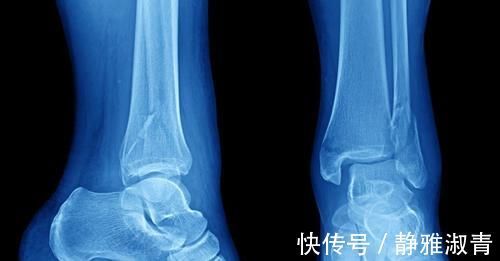

骨刺其实就是我们骨质增生比较严重,有些关节受到压迫软骨织磨损后自我修复出现增生的情况,这是人体衰老的正常现象之一。从某种方面来讲,骨质增生甚至可以看作是我们人体的自我恢复系统运转的结果,只有在骨质增生非常严重影响到我们日常生活,或者造成其他并发症的时候才需要进行治疗。